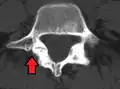

Anterolisthesis L5/S1 -

Anterolisthesis L5/S1. Blue arrow normal pars interarticularis. Red arrow is a break in pars interarticularis. -

Anterolisthesis L5/S1

Computed tomography (CT)

Computed tomography can be helpful in evaluating bony vertebral abnormalities, such as fractures.[38] This can be helpful in determining if the fracture is a new, old, and/or progressing fracture.[38] CT use in spondylolisthesis evaluation is controversial due to high radiation exposure.[39]